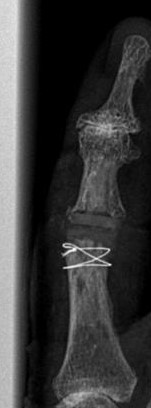

Blickfang ist hier das x-förmige Implantat zur Versteifung eines schmerzhaften und ehemals deformierten Endgelenkes.

Im Mittelgelenk fällt ein flauer "Schatten" von einem Kunstgelenk aus Silikon (Silikonendoprothese) auf.

14 Jahre nach Implatation einer Pyrrocarbon Endoprothese ist es hier zur vollständigen knöchernen Überbauung gekommen Rechts das postoperative Bild mit Entfernung des Knochens, der Prothese und Einbau eines Silikonspacers. Ein Draht sichert die Knochenschuppe, die Zur Entfernung abgehoben wurde. |